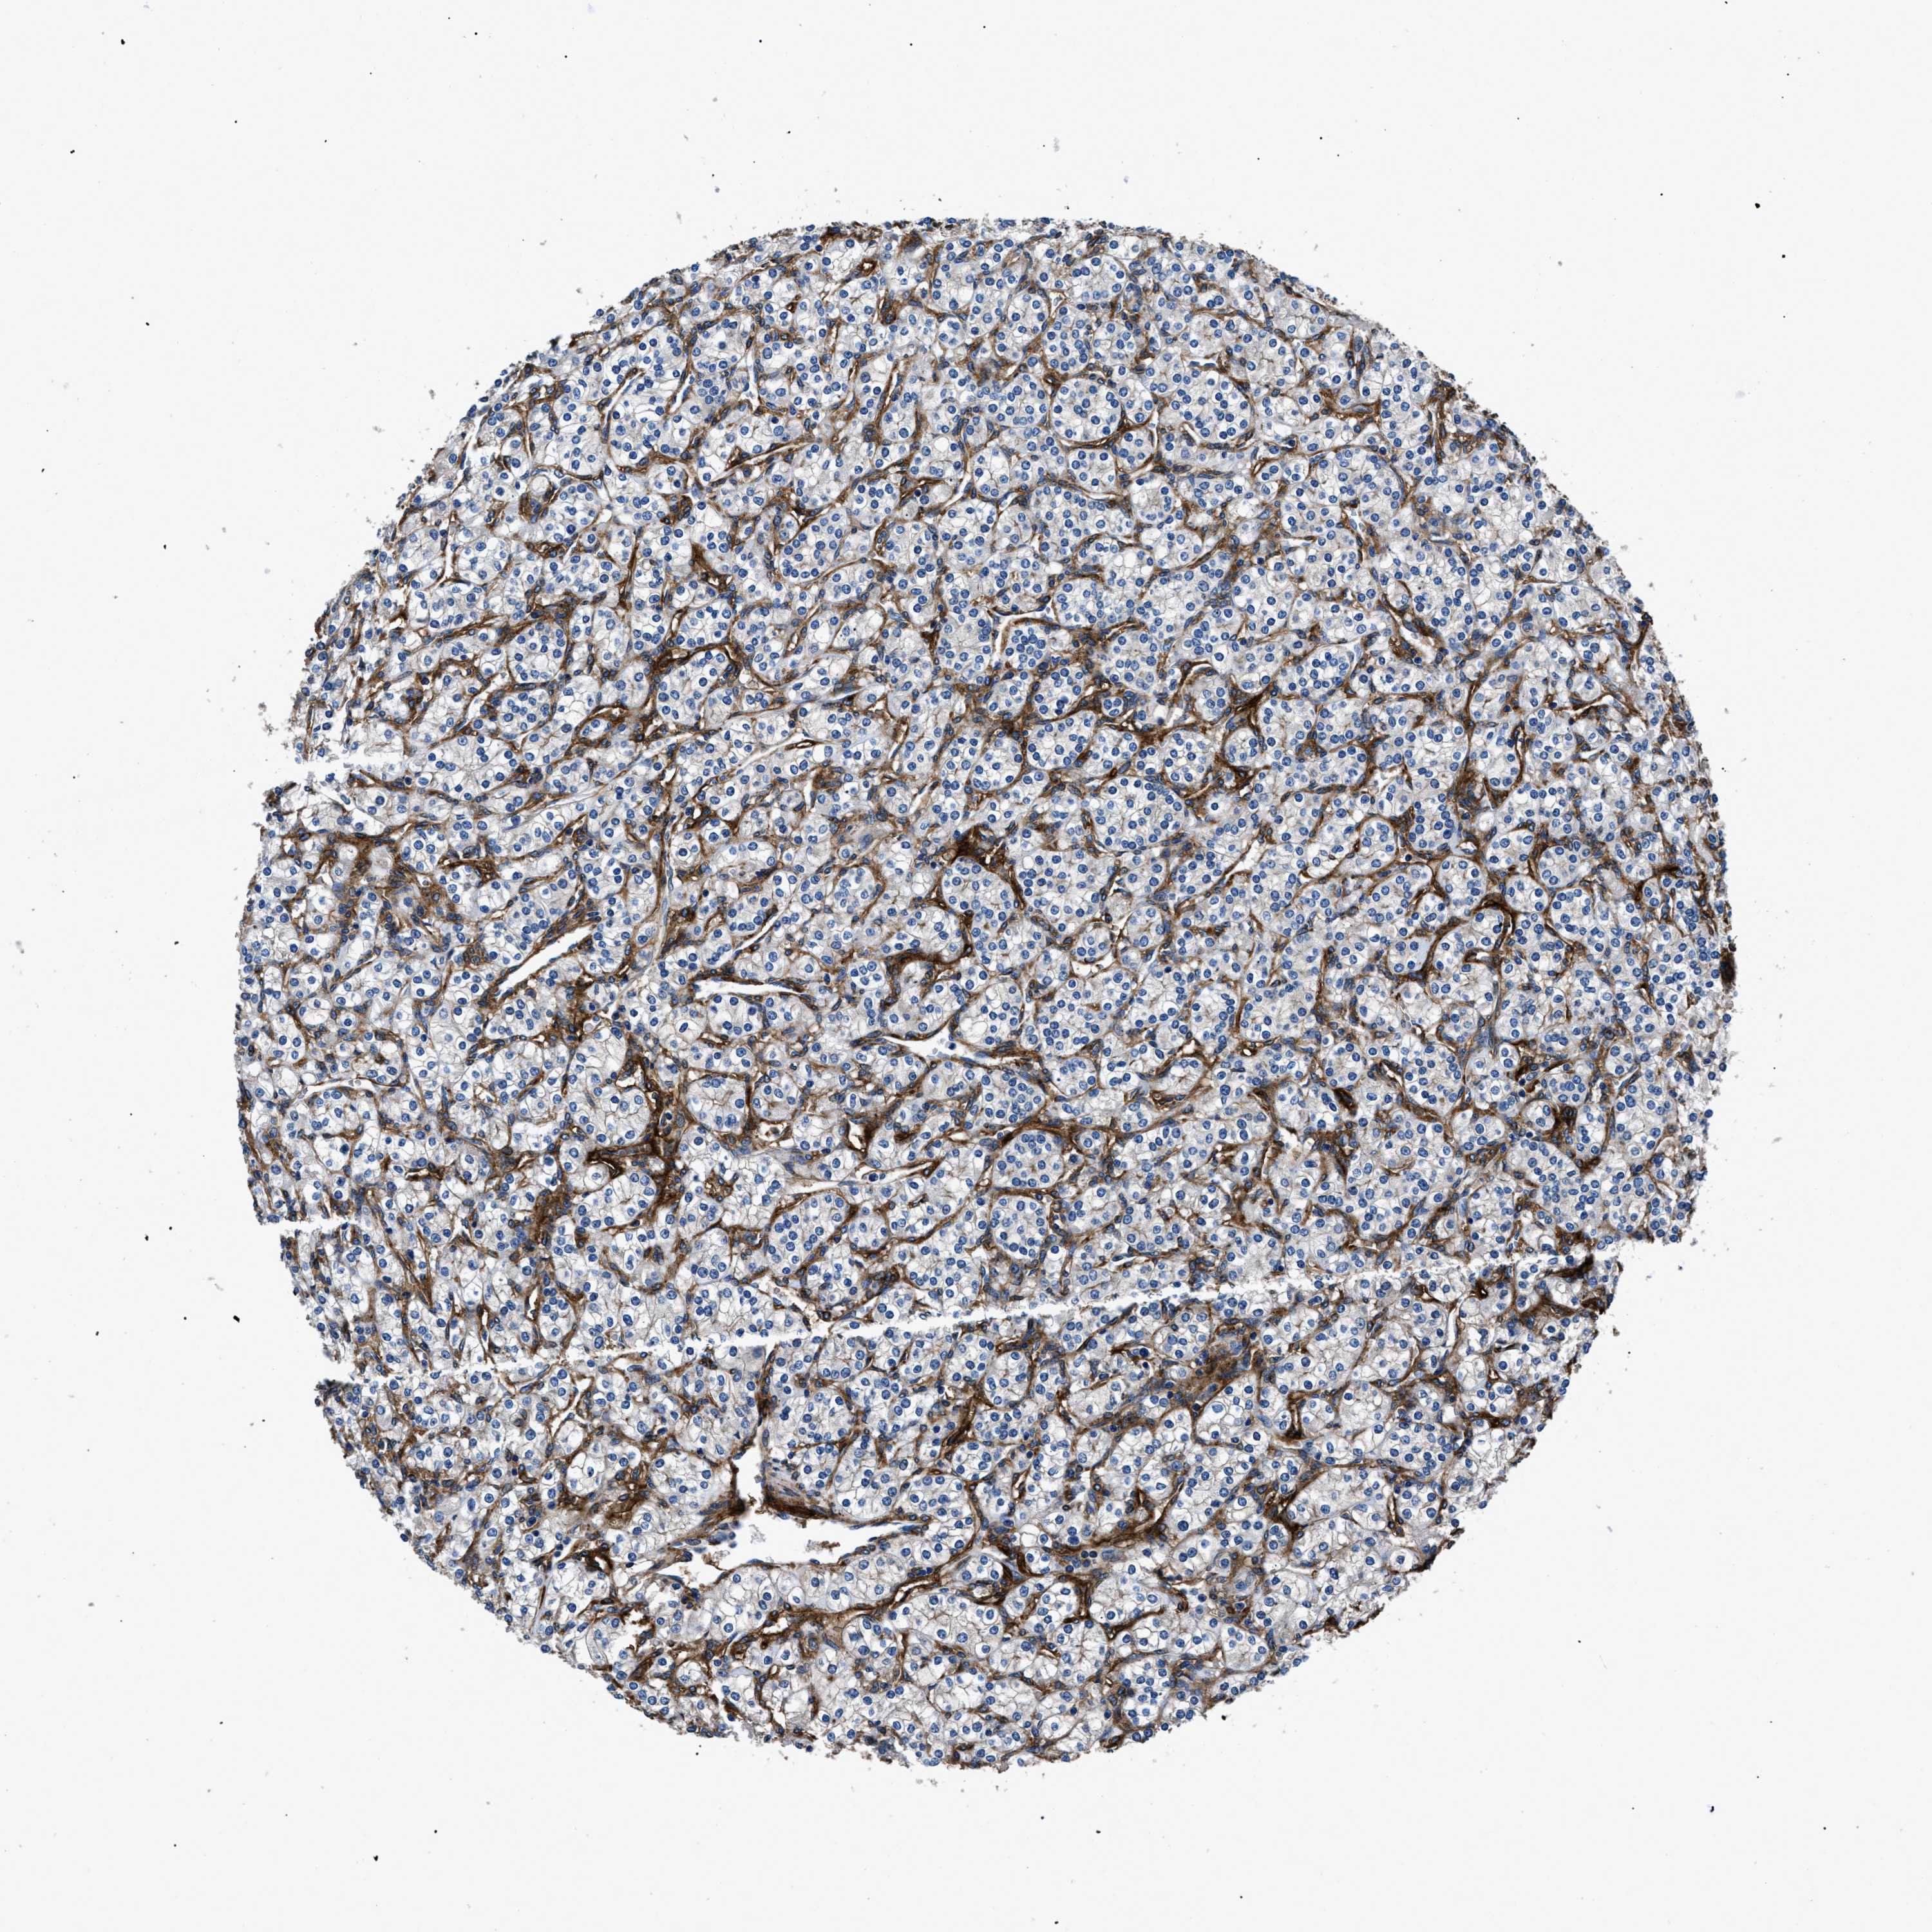

TCGA RNA samplesi

RNA-seq data is reported as average FPKM (number Fragments Per Kilobase of exon per Million reads), generated by the The Cancer Genome Atlas (TCGA) .

Normal distribution across the dataset is visualized with box plots, shown as median and 25th and 75th percentiles. Points are displayed as outliers if they are above or below 1.5 times the interquartile range. FPKM values of the individual samples are presented next to the box plot.

Average pTPM 29.8